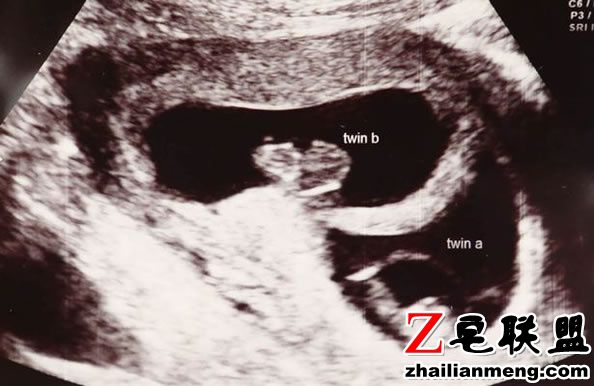

英国爱尔兰County Kilkenny 一对双胞胎出生相隔近3个月,姐姐Amy Elliott 急着与父母见面,在第23周时来到人世间。

而妹妹Katie Elliott 隔了87天后出生, 创下全世界出生时间相隔最远的纪录。

双胞胎母亲Maria Jones Elliott 2012年怀孕第23周时身体不适,送到医院治疗时羊水就破了,但是离预产期还有4个多月。